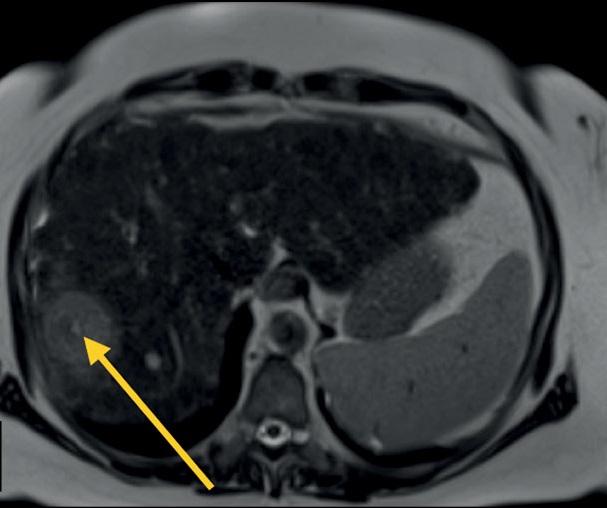

Magnetic resonance imaging is used for diagnosing abdominal and retroperitoneal space pathology, which allows visualizing focal or diffuse lesions in the parenchymal and hollow viscera with high diagnostic accuracy and reproducibility. Magnetic resonance imaging has advantages over computed tomography in the sensitivity and specificity of determining pathological changes in parenchymal organs, bile ducts and ducts of the pancreas, peritoneum, and retroperitoneal space.

The multiparametric protocol provides information about the mutual topography of organs and their structure and the functional state of tissues. This allows to move from structural to functional evaluation. In most cases, the standard abdominal protocol includes T1-weighted images, T2-weighted images, diffusion-weighted images, and magnetic resonance cholangiopancreatography. Depending on the objectives and patient’s condition, this protocol can be significantly reduced or supplemented.